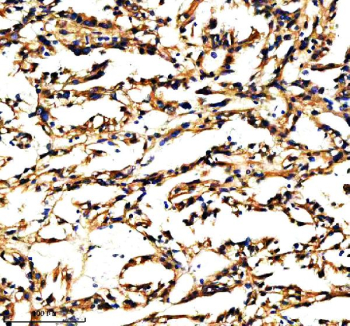

Immunohistochemical staining of PXDN using anti-PXDN antibody. PXDN was detected in a paraffin-embedded section of human clear cell renal cell carcinoma tissue. Heat mediated antigen retrieval was performed in EDTA buffer (pH 8.0, epitope retrieval solution). The tissue section was blocked with 10% goat serum. The tissue section was then incubated with 2 ug/ml rabbit anti-PXDN antibody overnight at 4oC. Peroxidase Conjugated Goat Anti-rabbit IgG was used as secondary antibody and incubated for 30 minutes at 37oC. The tissue section was developed using an HRP secondary and DAB substrate.